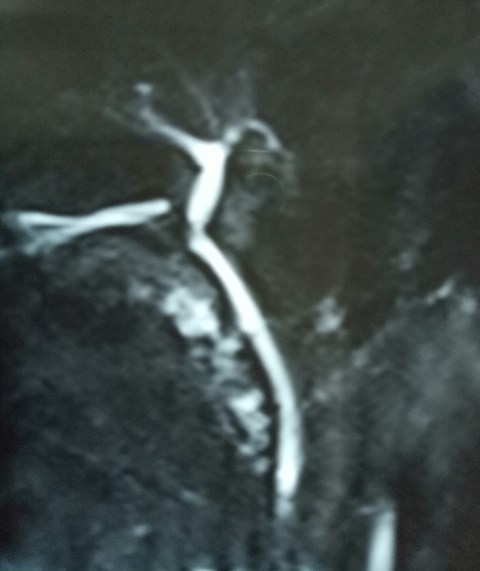

Another lap chole landing up in trouble. A young 30 years old male underwent a very difficult lap chole due to the frozen Calot’s triangle and a very thick walled gall bladder. Postoperatively had a bile leak which was 200 cc on the first postoperative day and then continued to decrease in amount gradually drying up in 18 days. MRCP shown below reported a small collection and a ? kink and narrowing at the site of cystic duct-CBD junction. Was it a cystic duct blow-out?